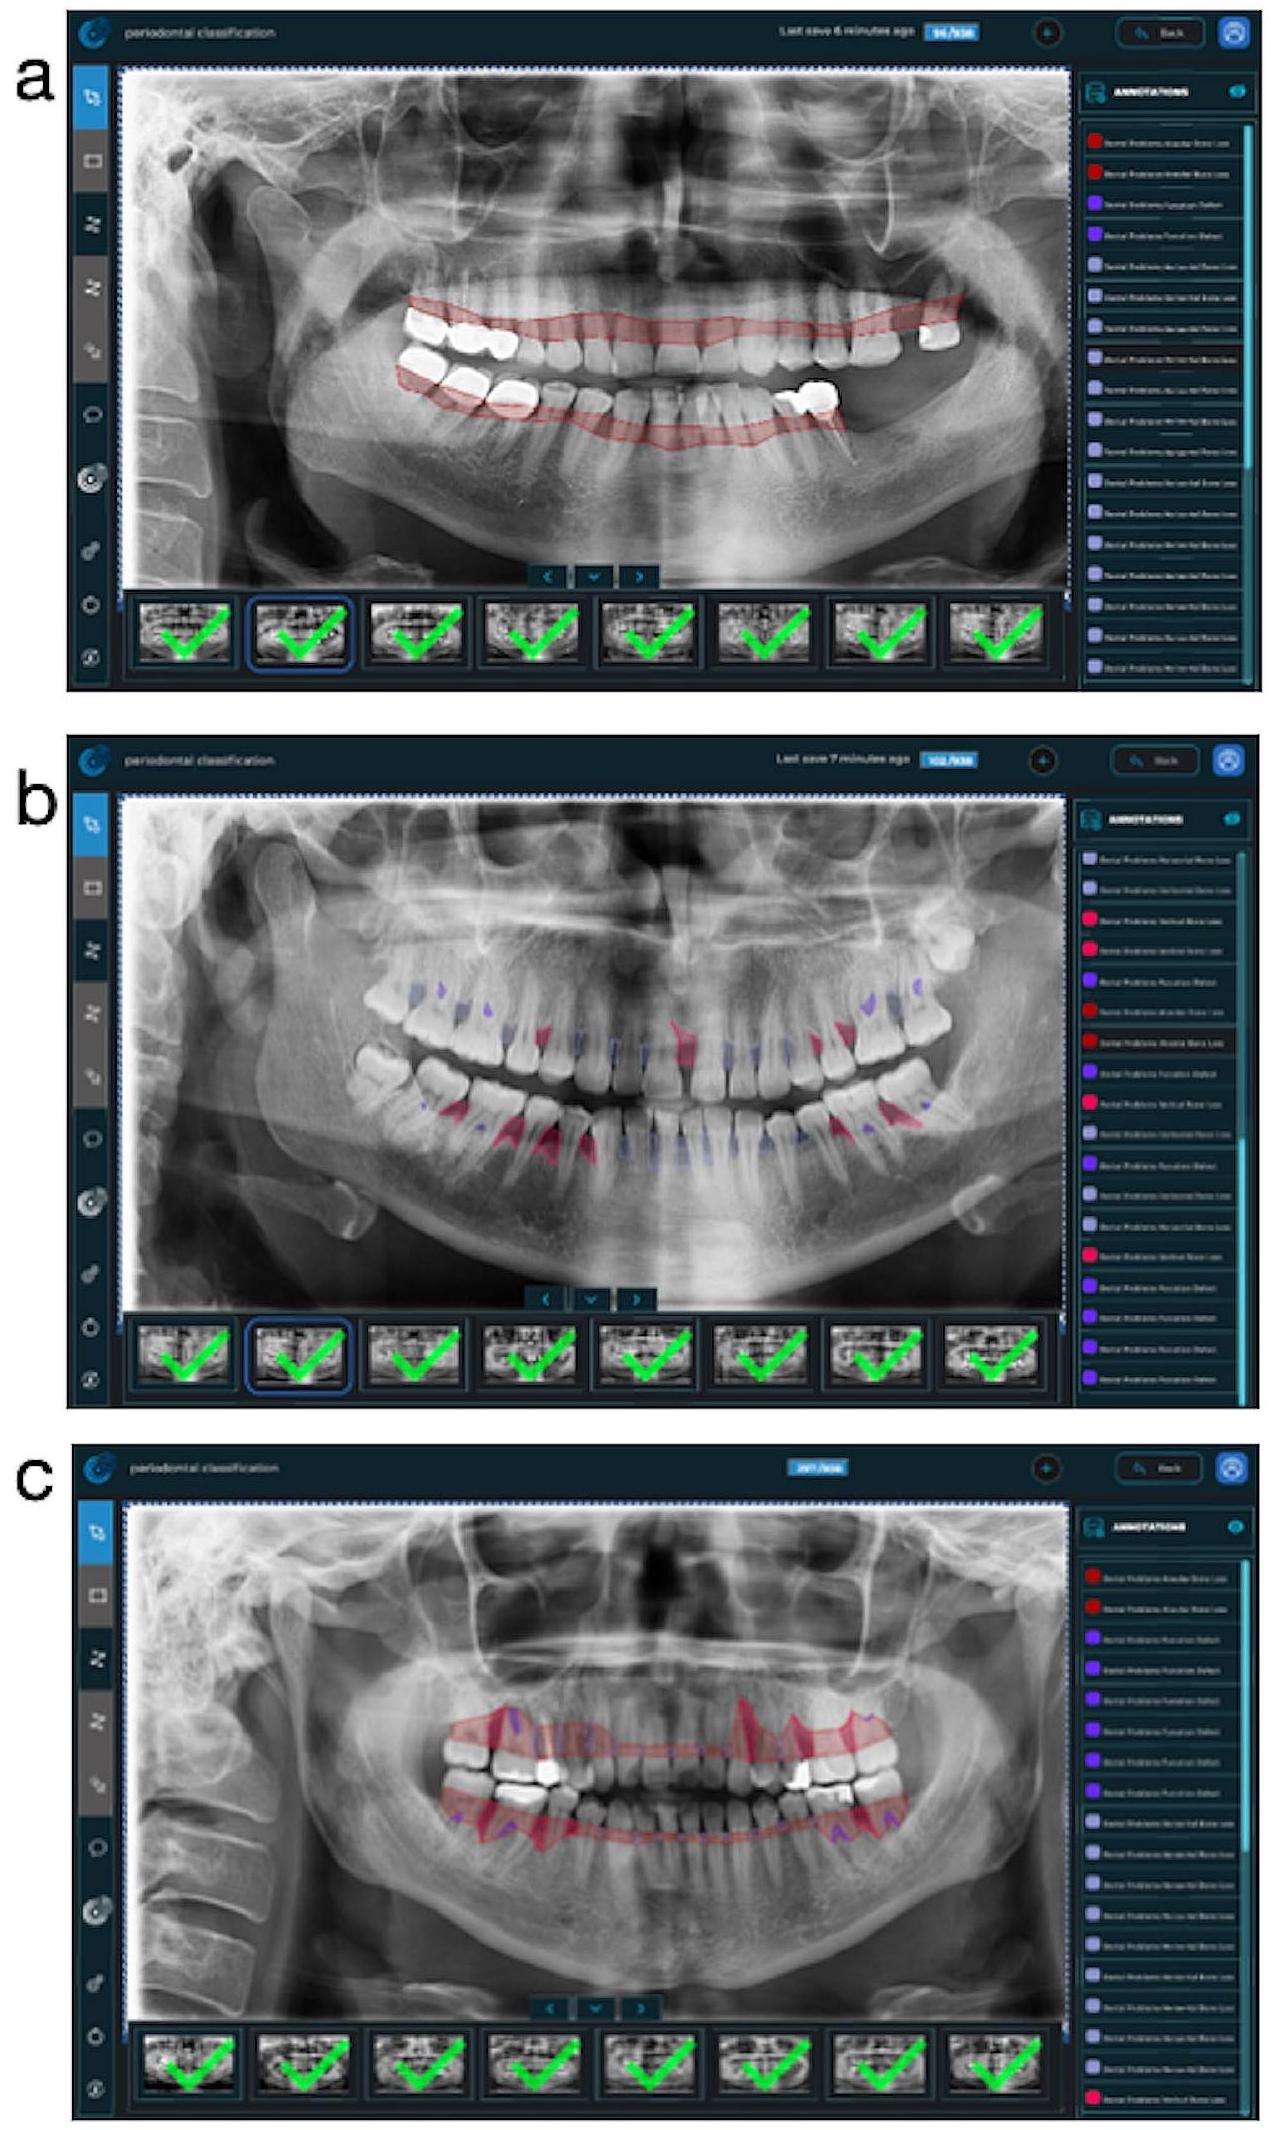

Ground truth

junction of all teeth. After that, the segmentation line was combined to follow the line on the distal surfaces of the most distal teeth and the border of the bone crests in the relevant jaw. In Fig. 1-a, an example image was presented to better understand the path followed when labeling this parameter. (Fig. 1-a)

تقاطع جميع الأسنان. بعد ذلك، تم دمج خط التقسيم ليتبع الخط على الأسطح البعيدة لأبعد الأسنان وحدود قمة العظام في الفك المعني. في الشكل 1-أ، تم تقديم صورة مثال لفهم أفضل للطريق المتبع عند وضع علامة على هذه المعلمة. (الشكل 1-أ)